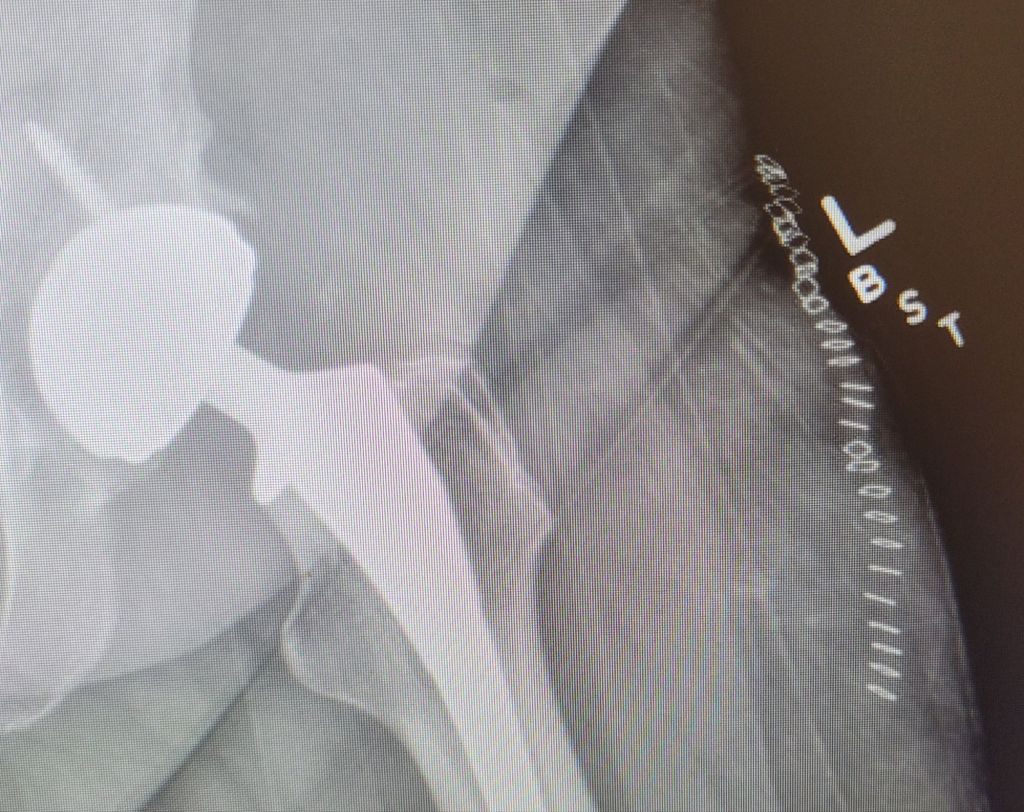

I am almost ready to cut myself loose. The staples are out. I am no longer using a walker nor trekking pole. After nineteen months of struggle, I am down to one bandaid on the part of the incision that is still smiling. I have tried to be still since the staples were removed three days ago. This cautious pause is due to the fact my other incision on the right hip got infected last July causing swelling at the site and fever. I do not want to repeat this with my left hip.